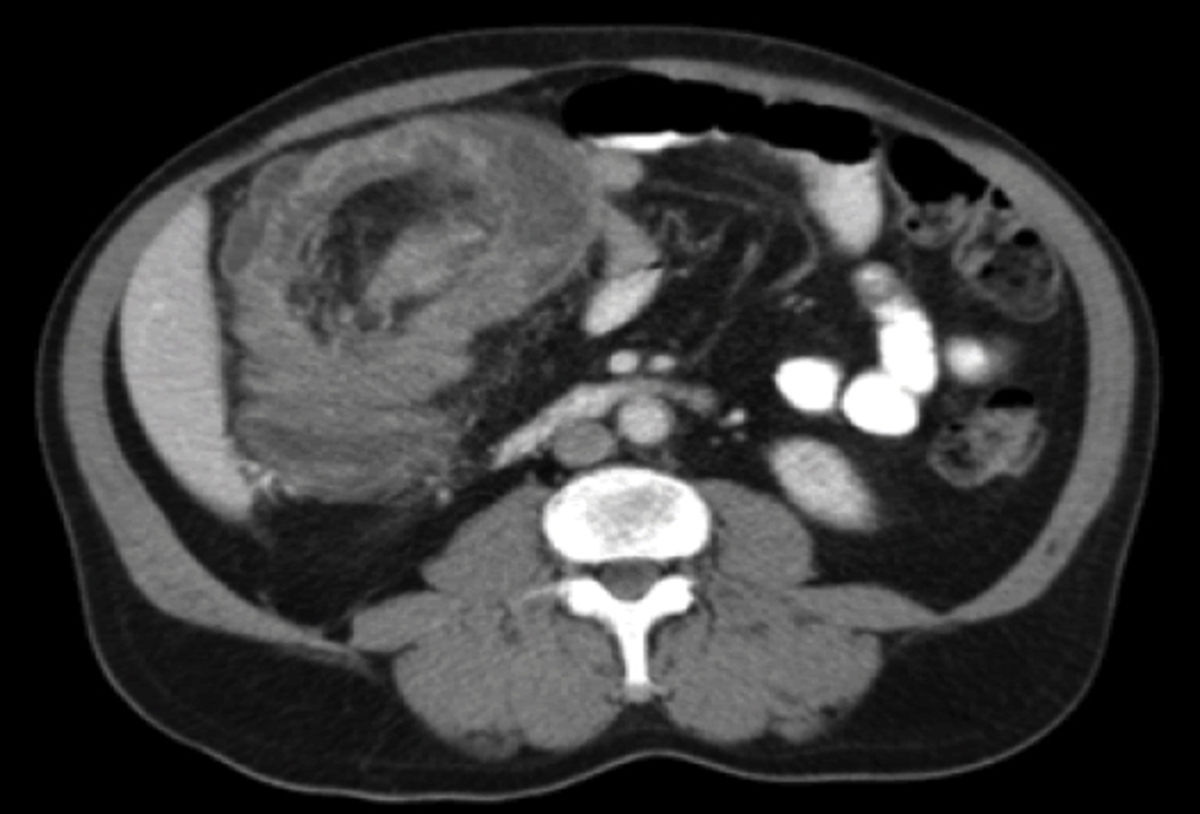

Physical examination revealed a BMI of 21, and an abdominal bruit, which intensified during expiration, but was barely audible at end-inspiration. Her epigastrium was tender to palpation but no organomegaly was present. Laboratory evaluation has been normal including a CBC, liver biochemical tests, amylase, lipase, BMP, and H. pylori antibody titers. EGD and UGI series revealed only a small hiatus hernia. Abdominal imaging is shown in the figure. A standardized test meal using Tc99m-labeled egg whites showed <10% of the radioisotope was present in the stomach at 4 hours. What is the most likely diagnosis?

• Celiac artery compression syndrome (CACS), also known as median arcuate ligament syndrome (MALS)

• compression of CA by MA ligament of the diaphragm

• Compression worsens with deep EXPIRATION as the diaphragm moves more caudally during expiration than does the CA

• Angiography in deep expiration has been the gold standard in the diagnosis of CACS in the past. One may see focal narrowing of the celiac axis with post-stenotic dilatation and increased collaterals from the superior mesenteric artery.

• Angiography has largely been supplanted by multidetector CT scanners which will show focal narrowing of the celiac axis with a characteristic “hooked” appearance.